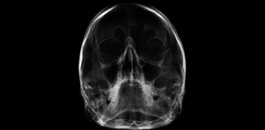

Avaliação das vias aéreas.